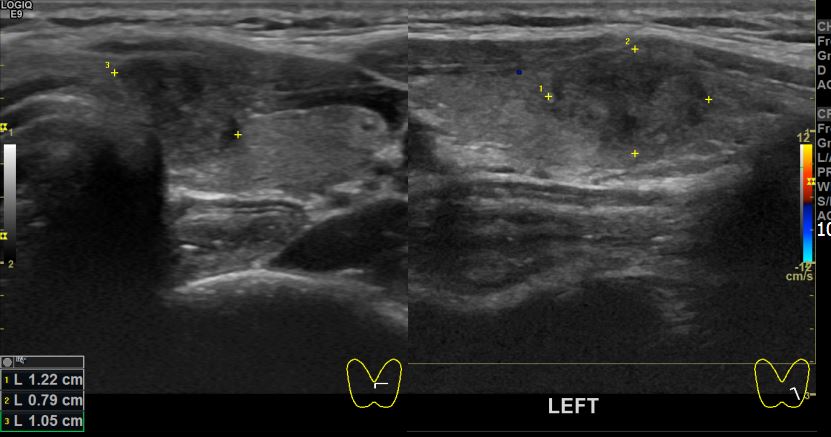

아산유외과개원후 48번째 갑상선암진단

상기환자 건강검진상 이상소견으로 내원하신 30대 여성분으로 좌측 의심스러운혹

세포검사진행후 갑상선암으로 진단되었습니다